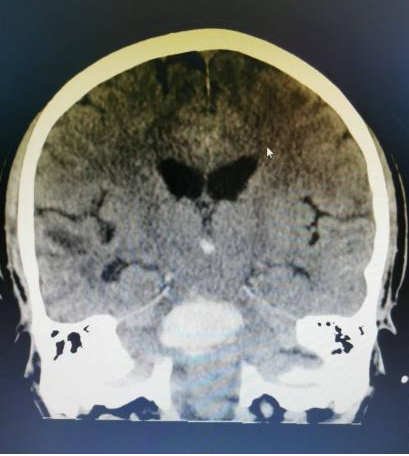

7月下旬的一天,正在开会的李老师突然意识不清伴恶心、呕吐不适,四肢僵直、小便失禁,于是呼叫“120”由我院急诊人员接回,行颅脑CT后提示脑干出血(脑桥出血伴脑内血肿)。

神经外科主治医师唐清明阅片后,诊断患者脑干血肿及呼吸衰竭明确,随时可能呼吸、心跳停止死亡,目前仅脑干血肿清除手术可能有机会挽救患者生命。

脑干出血既往属于神经外科手术禁区,但近年来随着神经外科设备的更新以及技术的飞速发展,我院神经外科团队不懈努力,目前已经熟练掌握此项手术技术。全院各科室争分夺秒,在李老师入院40分钟内其送入手术室,征得家属同意后,唐清明在显微镜下精细手术操作,历经2小时30分钟成功完成手术,术后复查CT提示脑干区血肿清除。术后1周患者恢复自主意识,目前正在康复过程中。